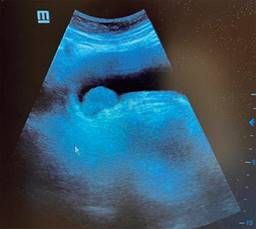

El cirujano general aborda particularmente problemas clínicos que incluyen el aparato digestivo, el cuello, la pared abdominal y los trastornos del sistema circulatorio y el tórax. Un artículo publicado en 2008, por Lindelius,15 demostró que la implementación del ultrasonido por parte del cirujano general en casos de dolor abdominal agudo incrementó en 7.9% la precisión diagnóstica. En la consulta cotidiana de la especialidad, incorporar el rastreo sonográfico al área explorada agrega minutos al examen clínico que aportan datos de notable valor por la objetividad y precisión. El abdomen suele ser el sitio que los cirujanos generales exploramos con más frecuencia. Es posible en una consulta cotidiana hacer todo el protocolo de ultrasonido de abdomen superior en minutos, que incluye ambos cuadrantes superiores y los flancos, pudiendo observar el hígado, la vesícula y los conductos biliares, ambos riñones, el bazo, parte del páncreas y, con ayuda del Doppler color, los principales vasos de la región como la vena cava inferior, la aorta abdominal, la vena porta, los vasos esplénicos y la arteria hepática. Puede haber limitantes como el contenido gástrico, el nivel de llenado de la vesícula biliar o la constitución del paciente y su capacidad de cooperar con el estudio. Pero con la práctica cotidiana, se adquieren las destrezas y el refinamiento suficientes para lograr, con la experiencia acumulada, producir imágenes de relevancia diagnostica inmediata. En la fase de entrenamiento, contrastar nuestros hallazgos con información disponible en la red, con los colegas imagenólogos, o cirujanos ya experimentados en ecografía, permitirá la retroalimentación y la tutoría esenciales de toda curva de aprendizaje. Tradicionalmente se consideraba que aquellos órganos que contienen una mezcla de líquido y gas (intestino, estómago) no son valorables por ultrasonido, el gas produce un efecto rarefacción, ya que no comprime las ondas como un tejido solido o un medio líquido, la señales entonces se dispersan impidiendo que regresen como ecos y permitan al procesador formar una imagen congruente con el órgano explorado. Sin embargo, cuando esta condición cambia como consecuencia de un estado patológico, es posible identificar el contenido intestinal o el gástrico y darnos una idea más aproximada de lo que realmente está ocurriendo en ese abdomen. Podemos, por ejemplo, saber si un estómago está lleno de líquido, o si el intestino contiene residuo sólido, líquido o gaseoso. Los equipos actuales pueden incluso ver en detalle la pared intestinal cuando ésta esté dilatada. Se puede distinguir cuando el colon está ocupado de líquido a nivel del flanco izquierdo como podría ser en una colitis amebiana o en una oclusión intestinal,16 donde se observa dilatación del intestino delgado ≥ 25 mm, el peristaltismo anormal, la presencia de líquido libre intraperitoneal y el edema de la pared intestinal (Figura 2). En casos de dolor abdominal agudo, el ultrasonido puede, en forma inmediata, permitir diagnósticos diferenciales como el hallazgo de una dilatación pielocalicial por nefrolitiasis (Figura 3), o un aneurisma de la aorta abdominal (Figura 4). Un estudio prospectivo realizado en Irvine, California,17 encontró que la a capacidad diagnóstica del médico de primer contacto practicando el ultrasonido para detectar una colelitiasis tiene una especificidad de 87% y una sensibilidad de 82%, mientras que la prueba de ultrasonografía realizada por radiología tuvo sensibilidad de 83% y una especificidad de 86%. Es decir, que, ahorrando tiempo al paciente, el diagnóstico de colelitiasis es factible agregando unos minutos al examen físico inicial. En casos de apendicitis, el método diagnostico considerado como el estándar de oro es la tomografía axial computarizada (TAC). Sin embargo, tiene inconvenientes como su disponibilidad, su costo, el riesgo de radiación en niños y pacientes embarazadas. En tales situaciones, sobre todo en niños, sexo femenino o pacientes delgados, el ultrasonido es una poderosa herramienta que complementa el examen clínico inicial. Las ventajas del ultrasonido frente a la tomografía serian su ubicuidad (ya está en la sala de emergencias), el bajo costo, la ausencia de radiación y el diagnóstico diferencial con causas ginecológicas o genitourinarias de dolor. En apendicitis, la sensibilidad y especificidad de la TAC es de 99.4% y 80.0%, respectivamente. Para el ultrasonido, la sensibilidad diagnóstica es de 83% y la especificidad de 90%. La tasa de apendicectomía negativa es ligeramente mayor en el grupo de TAC que en el del ultrasonido, es decir, 7.1% (3/42) (TAC) en comparación con 4.67% (5/107) (ultrasonido). Hay que recalcar que el ultrasonido es operador dependiente. La experiencia y la calidad del equipo juegan un papel importante.18 La apendicitis tiene varios hallazgos característicos, como la pared edematosa y el aumento de grosor general. Se toman para criterios de positividad una estructura tubular aperistáltica no compresible que mide más de 6 mm de diámetro en el cuadrante inferior derecho (Figura 5).19-21

Figura 4: Aneurisma abdominal. Hallazgo incidental en la consulta de un paciente que acude por un cuadro de dolor abdominal por herpes zóster.